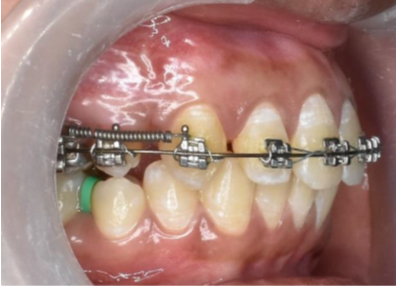

Chlorhexidine 0.12% oral rinse.Maxillary canine retraction was then initiated after 10 days of surgical procedures on 0.018 inch round Australian SS archwire using a NiTi closing coil spring (Leone, Italy) extending from hook on maxillary first molar to the power arm of maxillary canine applying a force of approximately 150gm calibrated with a Dauntrix gauge as shown in ([Figure 6]). Rate of canine retraction was followed up till 16, 12 weeks and 16r 4 weeks (T1), 8 weeks (T2),